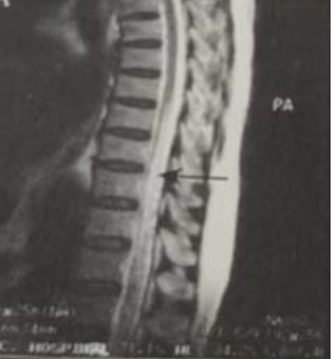

9)椎管造影(图1):见较脊髓表面长节段的异常迂曲蚯蚓状充盈缺损。

图1 T8~T12水平髓内长T2信号,可见脊髓表面弯曲的蚯蚓状或索状流空影[1]

脊髓MRI是诊断脊髓血管畸形比较敏感的辅助检查手段。其实,本例在MRI上的表现比较典型,可以见到蚯蚓状的脊髓流空影。但是,这种影像需要与脑脊液的流空影进行鉴别。前者常为蚯蚓状、匍匐状、串珠状等,而后者多为斑点样。另外,单纯从髓内病变的影像上看,还需要与脊髓空洞症